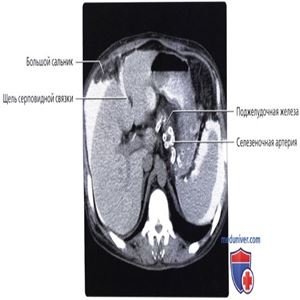

Серповидная связка поддерживает печень с передней брюшной стенки. Большой сальник лежит между кишечником и передней брюшной стенкой.

Жидкость проникает в щель серповидной связки. Обратите внимание на отсутствие жидкости в сальниковой сумке. В большинстве случаев за исключением тех, когда